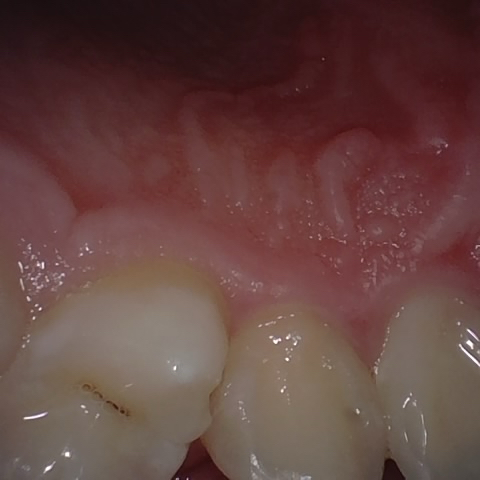

Annotated as "Good"